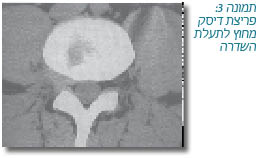

- בתמונה 2 נראה דיסק פרוץ בתוך תעלת השדרה ובתמונה 3 - דיסק פרוץ מחוץ לתעלת השדרה. בשני המקרים מדובר בתסמונת סכיאטית הנגרמת על ידי צניחת הדיסק הבין חולייתי, אלא שבמקרה הראשון, להזרקה האפידורלית הניתנת אל תוך תעלת השדרה, קיים סיכוי שהיא תהיה יעילה, ואילו במקרה השני, הסבירות שהזרקה לתוך תעלת השדרה תביא לשיפור היא נמוכה ביותר. יצוין שמיקום הדיסק הפרוץ (בתוך תעלת השדרה או מחוצה לה) אינו מצוין במרבית המחקרים הבוחנים את יעילות ההזרקה האפידורלית;